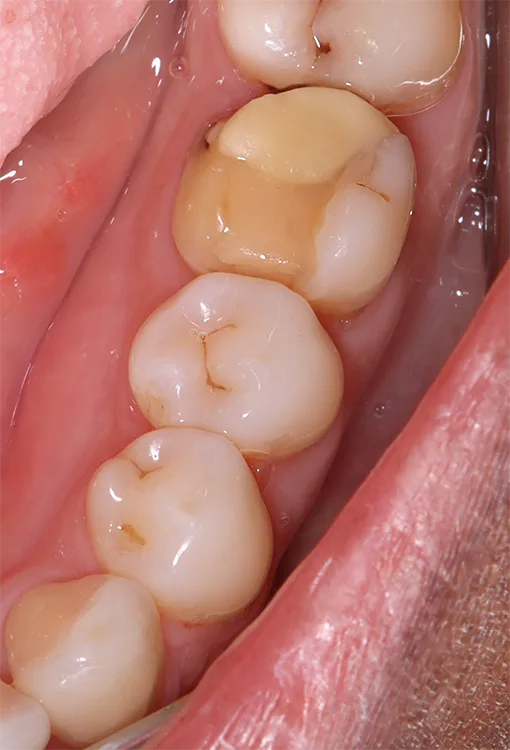

Die additive Fertigung von festsitzendem Zahnersatz kann in zwei weitere Gruppen eingeteilt werden: der provisorische Zahnersatz sowie der definitive Zahnersatz (Abb. 4a und b). Die Anforderungen für permanente Restaurationen sind deutlich höher, was erklärt, weshalb nicht jedes Komposit bzw. Material für definitive festsitzende Restaurationen zugelassen ist.

Die Hauptindikation der additiv gefertigten Restaurationen sind Einzelzahnrestaurationen wie Inlays, Onlays, Veneers, Teilkronen oder Vollkronen (Abb. 5). Aber auch der Einsatz als kurzspannige Brücke (provisorisch oder definitiv) ist möglich (Abb. 6). Der Einsatz additiv hergestellter Non-Prep-Langzeitprovisorien stellt eine außerordentliche Indikation dar und wird von den Herstellern nicht aufgeführt (Abb. 7).